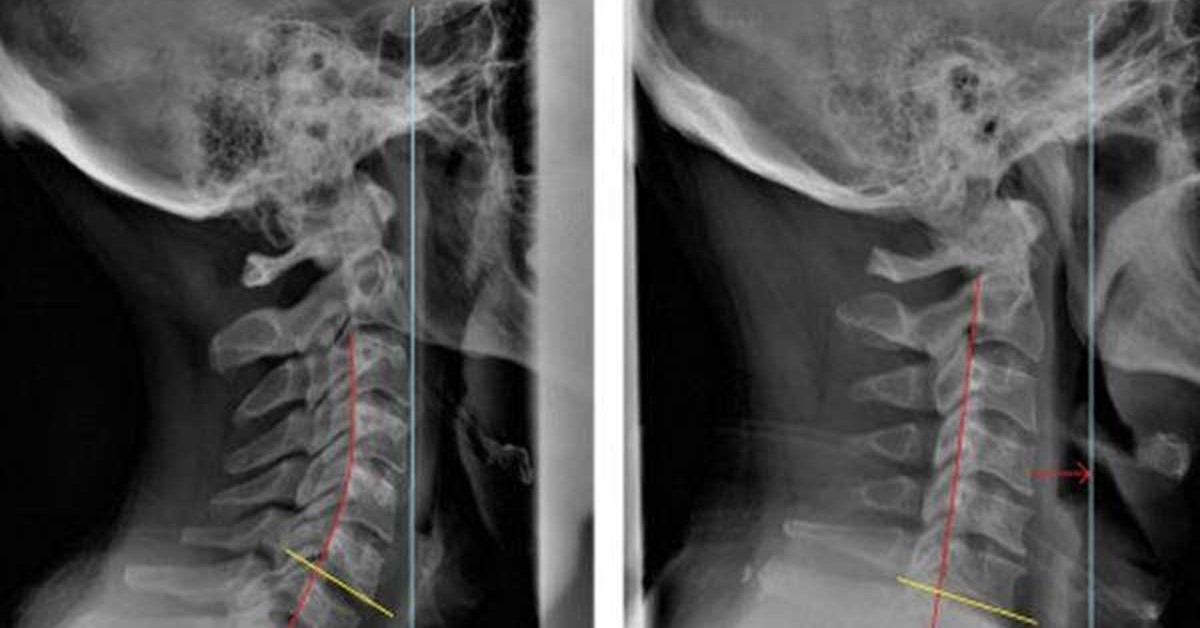

Thoái hoá cột sống xảy ra ở đâu

Thoái hoá cột sống xảy ra ở cả cột sống cổ, cột sống lưng (bao gồm lưng trên và lưng giữa), cột sống thắt lưng. Trong đó thường gặp nhất ở cột sống cổ và thắt lưng do đây là vị trí chuyển động và chịu tải trọng, áp lực nhiều nhất.